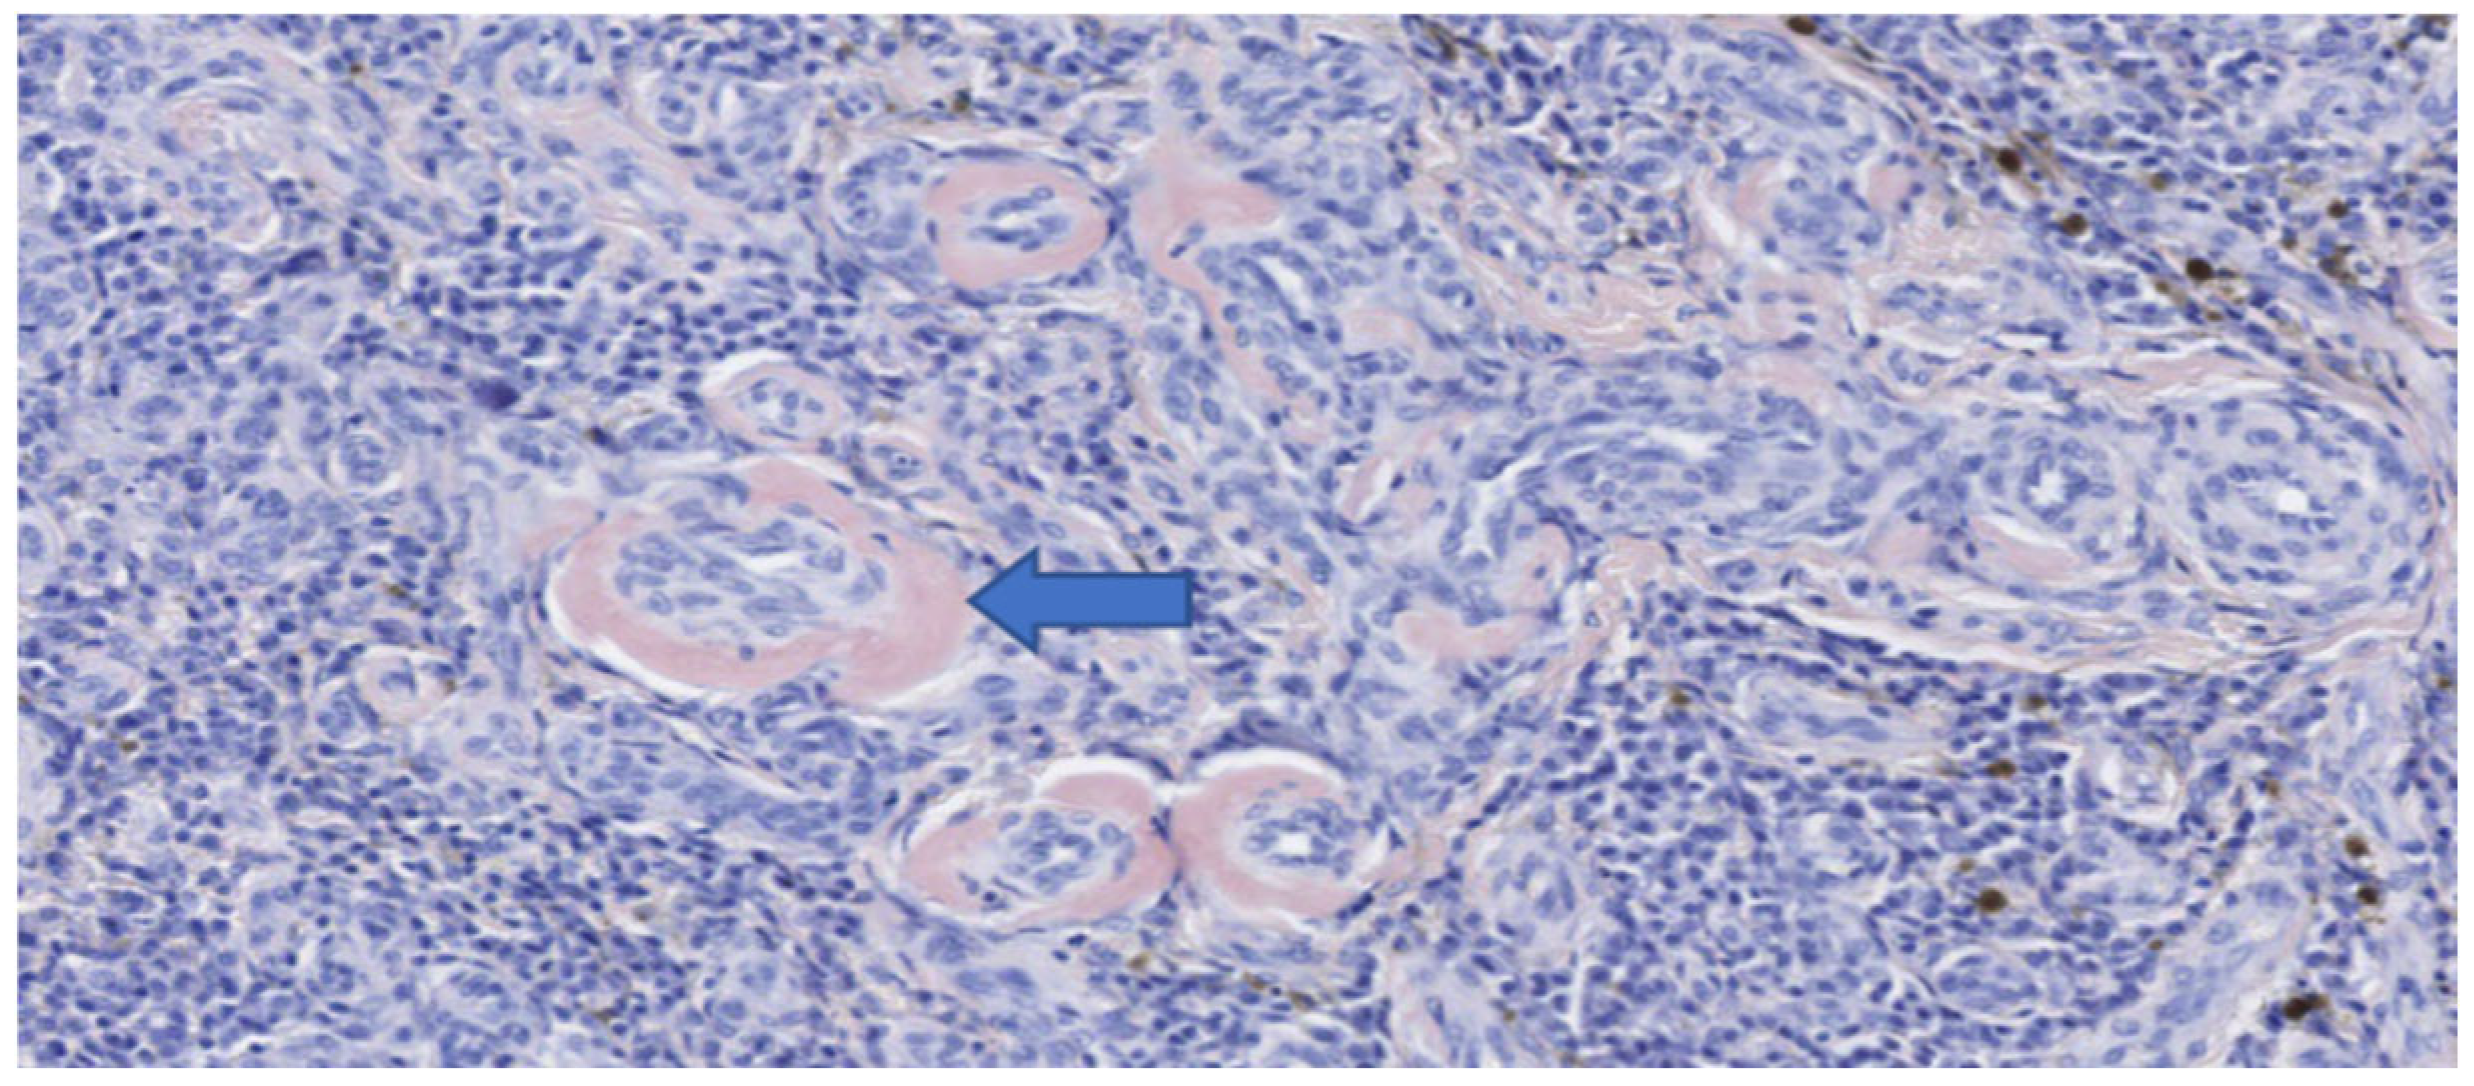

Figure 8.

Histopathology of the esophageal mass after surgical excision (Congo red stain). Positive intramural accumulations of amyloid (blue arrow).